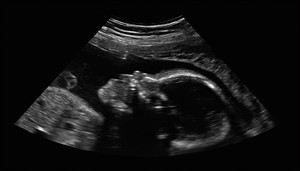

Các bác sĩ ở Ấn Độ rất kinh ngạc sau khi phát hiện có 8 phôi thai trong cơ thể một bé gái 21 ngày tuổi.

Một bé gái 7 tháng tuổi, ở Gujarat, Ấn Độ từ khi sinh ra đã trong tình trạng hiếm hoi mang thai người em song sinh.